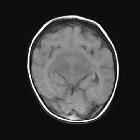

semi-lobar holoprosencephaly

Semilobar holoprosencephaly is a subtype of holoprosencephaly characterized by incomplete forebrain division. It is intermediate in severity, being worse than lobar holoprosencephaly and better than alobar holoprosencephaly.

As will most cerebral structural congenital abnormalities, semilobar holoprosencephaly is visible on all modalities, but in general is identified on antenatal ultrasound, and best characterized by MRI.

The basic structure of the cerebral lobes are present, but are fused most commonly anteriorly and at the thalami and there is partial diverticulation of brain (dorsal cyst). Features include :

- absence of septum pellucidum

- monoventricle with partially developed occipital and temporal horns

- rudimentary falx cerebri: absent anteriorly

- incompletely formed interhemispheric fissure

- partial or complete fusion of the thalami

- absent olfactory tracts and bulbs

- agenesis or hypoplasia of the corpus callosum

- incomplete hippocampal formation

An easier approach might be to assess fusion of more than 50% of the frontal lobes which might be suggestive of semilobar holoprosencephaly .